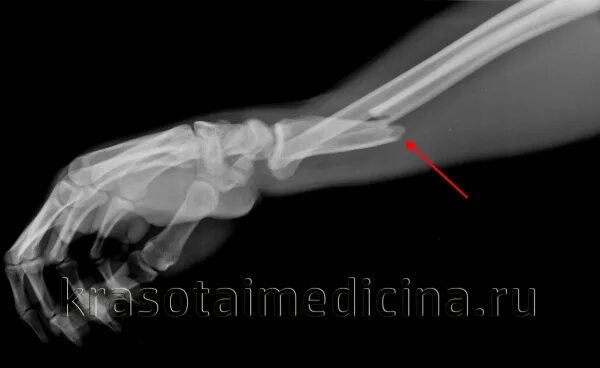

Закрытый перелом предплечья код по мкб 10